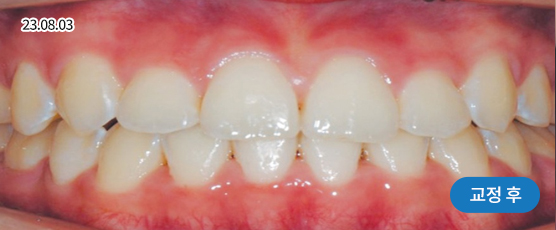

매복치 Solution

매복치는 잇몸 속에서 인접 치아에 손상을 줄 수 있어

치아 견인을 통해 제자리를 찾아주어야 정상적으로 치아가 자리 잡을 수 있습니다.

* 치근흡수, 잇몸퇴축 등 부작용이 발생할 수 있습니다.

* 본 사진은 동일 조건에서 촬영되었으며, 환자 본인의 동의를 얻어 게재되었습니다.